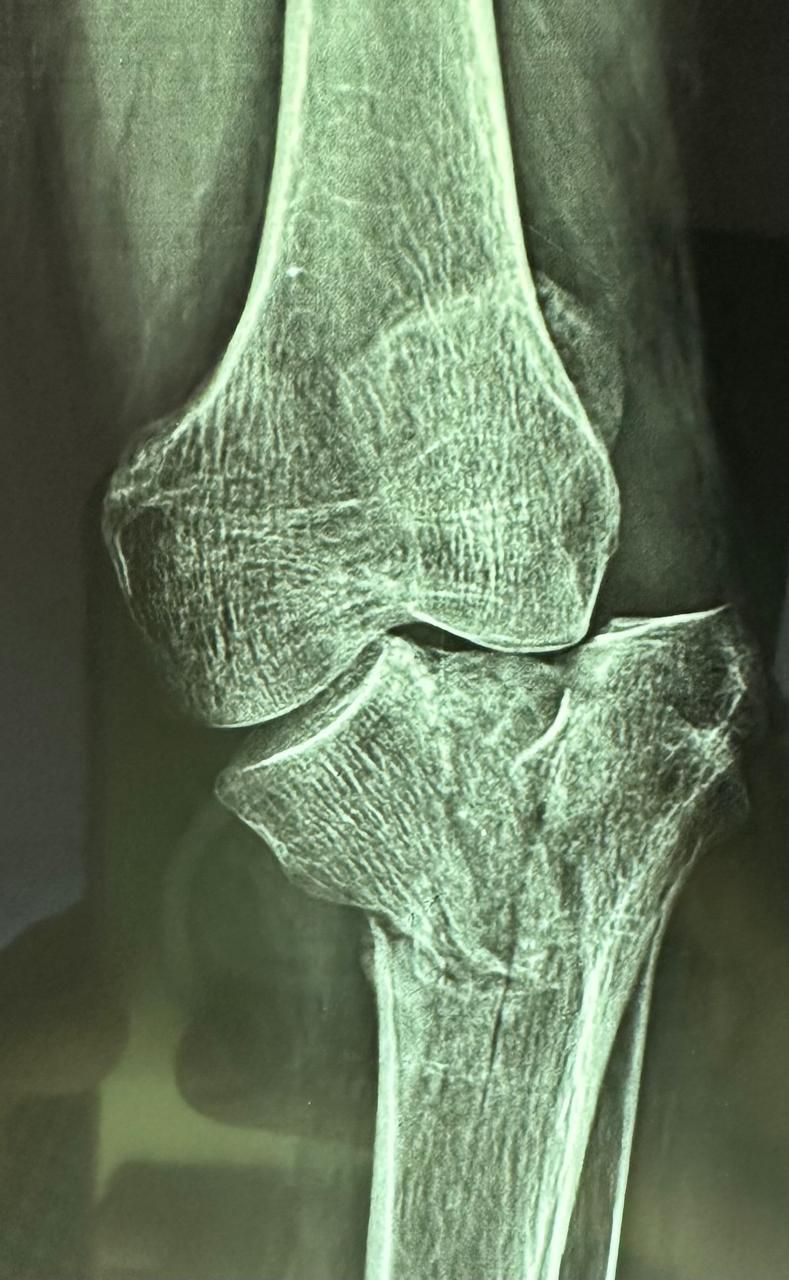

La ortopedia se enfoca en las enfermedades y alteraciones del sistema músculo-esquelético, tanto en adultos como en pacientes jóvenes. El Dr. Juan Carlos Torres Archila, especialista en ortopedia en Comitán, Chiapas, ofrece atención integral y personalizada para afecciones crónicas, degenerativas o congénitas que afectan huesos, articulaciones, músculos, tendones y ligamentos.

Cada caso es valorado a profundidad para proponer tratamientos conservadores (rehabilitación, ejercicios, ortesis) o procedimientos quirúrgicos cuando son necesarios, como artroplastías (colocación de prótesis articulares) o cirugías mínimamente invasivas como la artroscopía.